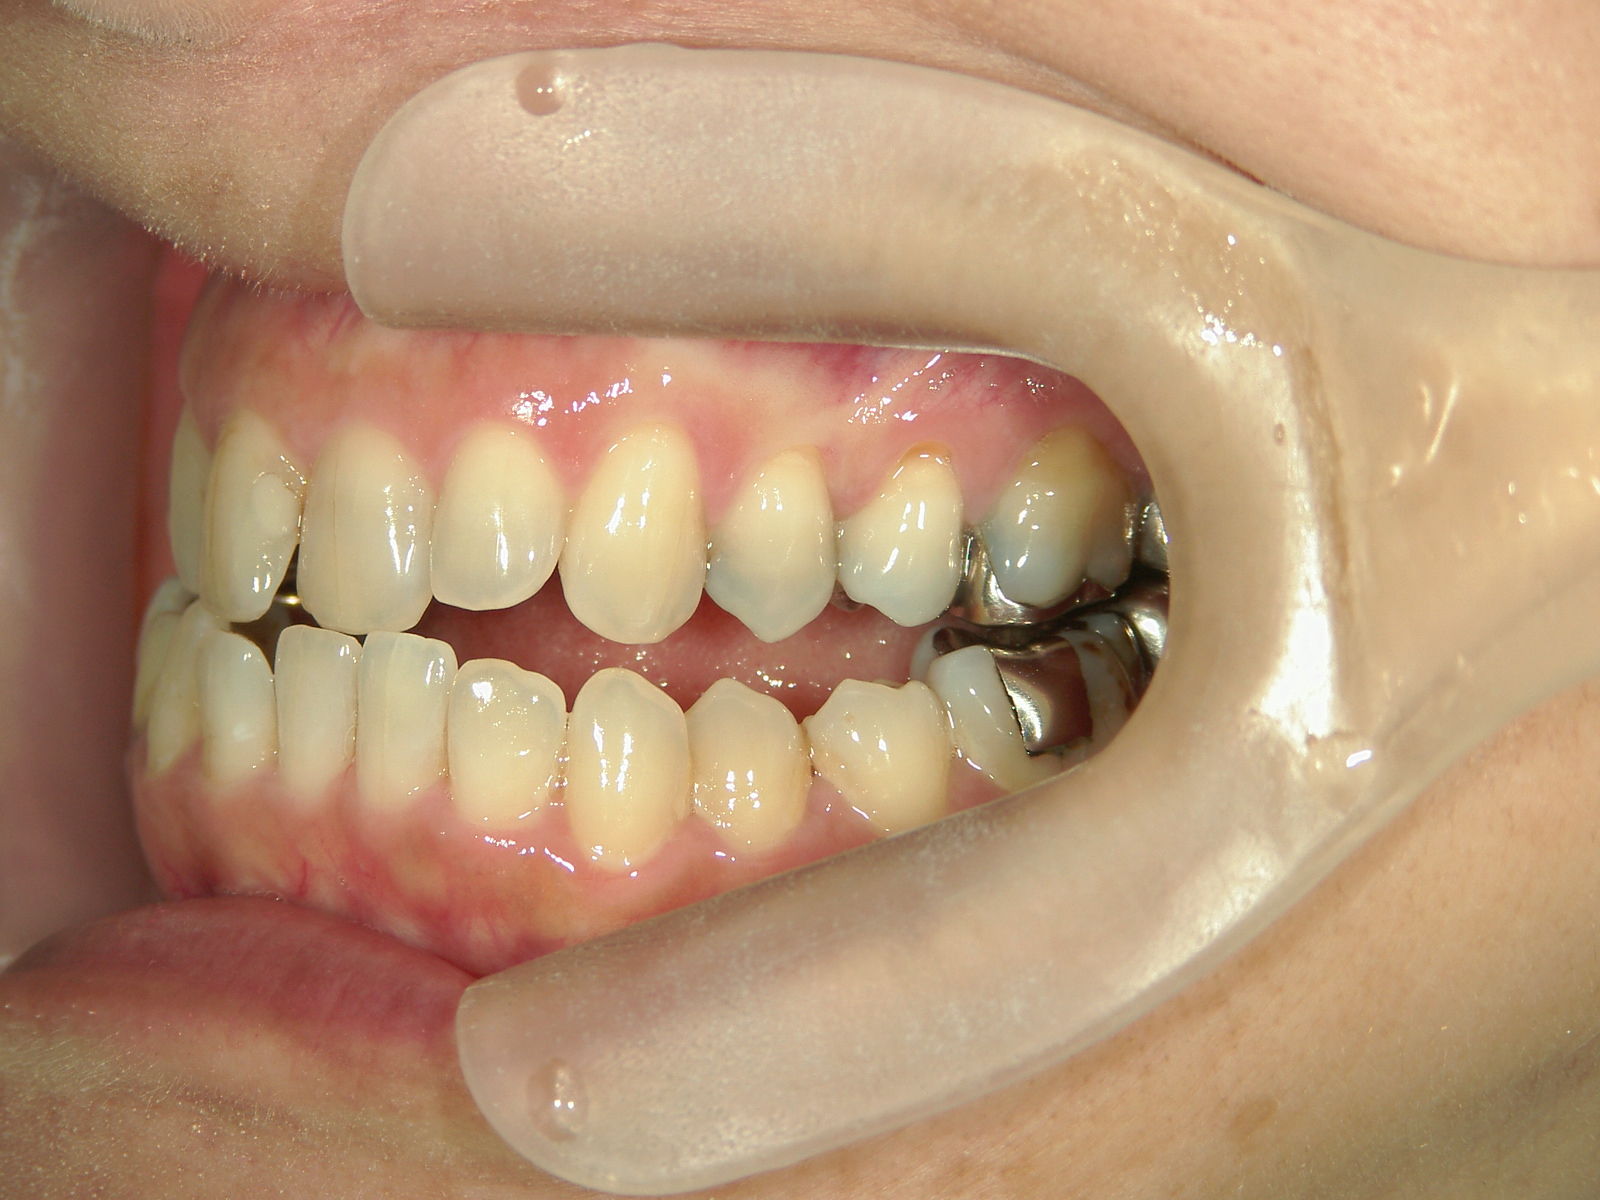

インビザライン矯正 症例(30)

主訴: 受け口、歯並びが気になる。

①患者様はインビザライン矯正をご希望でしたが、上顎骨が小さく、受け口になっているので、インビザライン矯正で治療するために「骨切断OPE」「矯正装置(MSE+フェイスマスク)」で上顎骨を拡大しました。

②右上前歯が内側に入っているため、歯列に入る隙間を作るためにワイヤー矯正を併用し、右上前歯を出しました。

③矯正装置を除去し、インビザライン矯正で歯列を整えました。